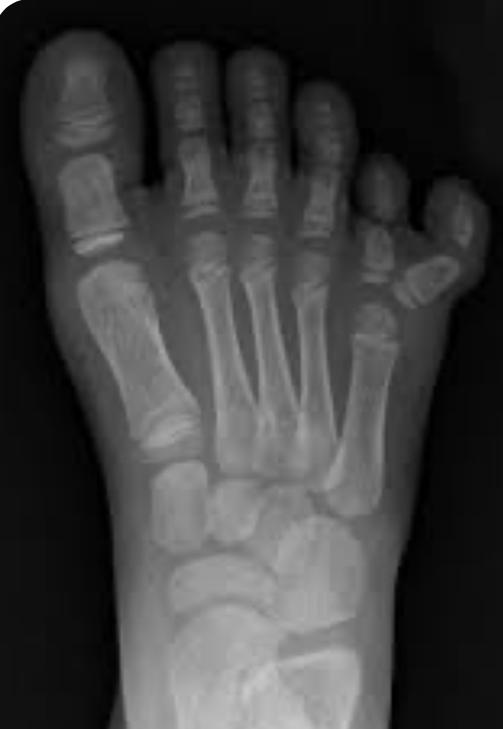

وأشار الدكتور صبري زيادة أنه يتم التشخيص سريراً، بوجود أصابع إضافية في القدم شعاعياً إذ يتوضح وجود عدد إضافي في عظام القدم،إما مشط إضافي للقدم أو عظم سلاميات إضافي في الأصبع(السادس الإضافي) في قدم الطفل.

وأبان استشاري جراحة العظام بالحمادي إلى أن نسبة حدوث الأصابع الزائدة من 1إلى 500 ولادة،ويكون العلاج باستئصال الإصبع الزائد في عمر 9إلى 12 شهراً إن أمكن،ويمكن إزالة الزوائد الجلدية الصغيرة بعد الولادة في أي وقت.